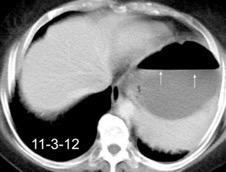

Parálisis frénica transitoria tras cirugía de válvula aórtica

Parálisis frénica transitoria post cirugía cardiaca (10%).

Puede acompañarse de atelectasia del LII.

Benjamin JJ et al. . Left lower lobe atelectasis and consolidation following cardiac surgery: the effect of topical cooling on the phrenic nerve. Radiology 1982